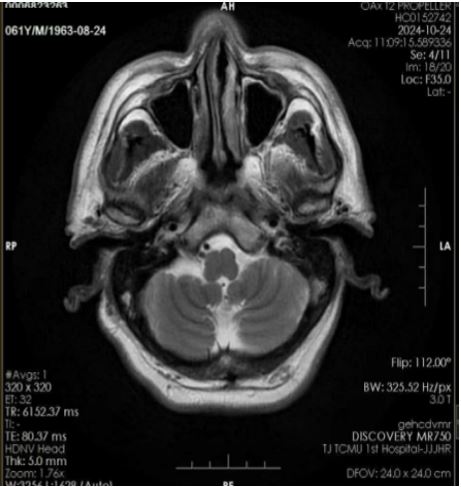

Acupuncture Can Promote the Rehabilitation of Swallowing Function in Post-Stroke Dysphagia and Improve the Success Rate of Nasogastric Tube Removal

Dan Liu, Rachana KC, Wenhui Wang, Yuanzhen Yang, Shu Wang, Zhang Lili, Unita Shrestha

A Case Report | 25 Sep 2025

Acupuncture Can Promote the Rehabilitation of Swallowing Function in Post-Stroke Dysphagia and Impro...